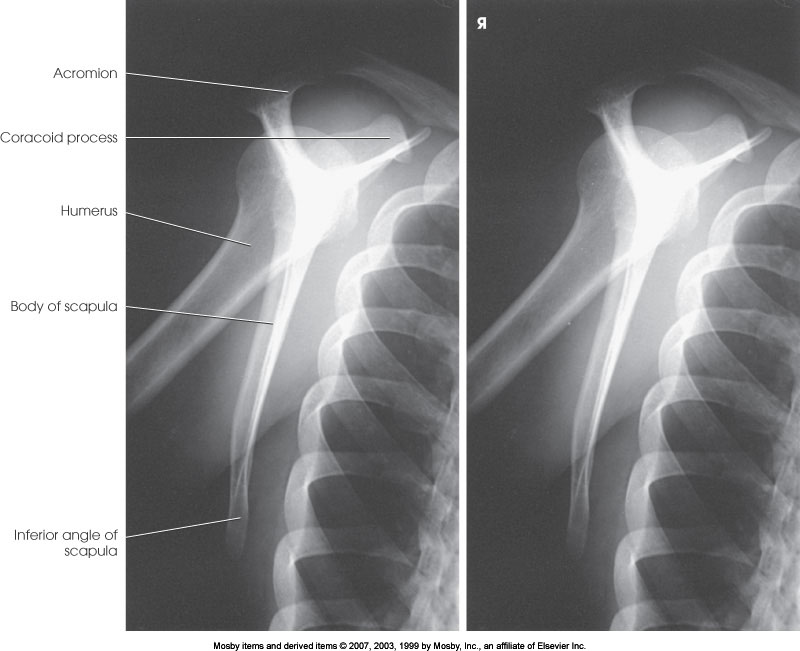

PA Oblique Shoulder (Y-View)

What position is demonstrated?